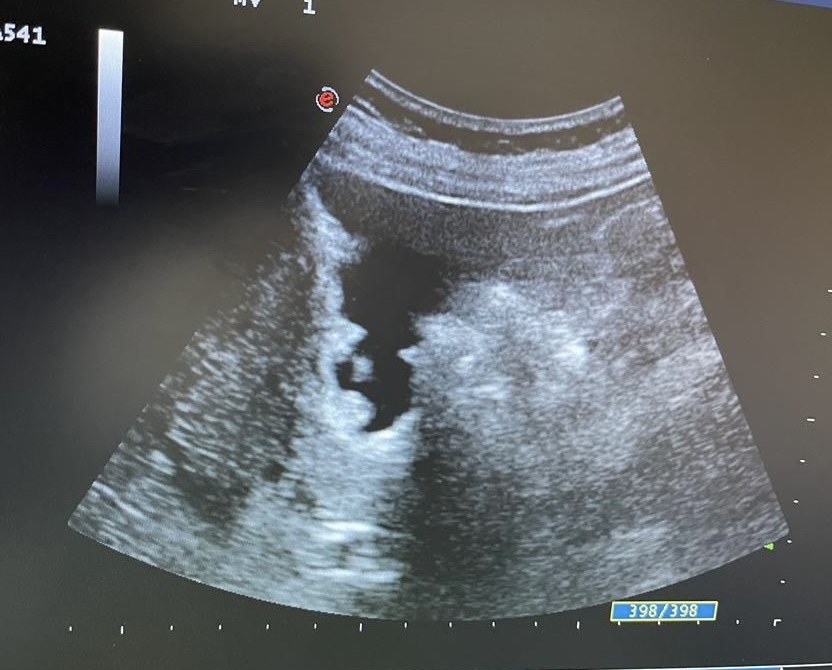

Mentalmente describí las lesiones,  se trata de lesiones múltiples hiperecogénicas  y adheridas a la pared vesicular y que no producen sombra posterior.

Confirmé que no se trataba de colelitiasis sino que en mi opinión eran múltiples pólipos vesiculares y alguno de ellos cercano a 1 cm de diámetro, sin poder descartar malignidad con la ecografía, por lo que solicité un TC abdominal que informó de un único pólipo vesicular de 6 mm.

Desde la consulta de cirugía se solicitó ecografía reglada y control en 6 meses que informó de múltiples engrosamientos nodulares en relación con pólipos (más de 10), los de mayor tamaño alcanzan 9 mm de grosor máximo. Alitiasica.